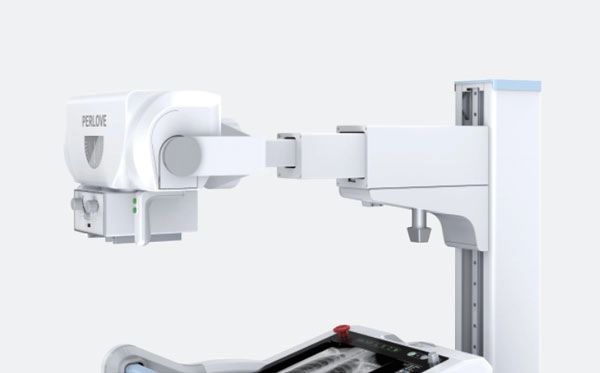

Mobile, accurate and versatile:

PLX5200A 50kW version are widely used in radiology, ward, ICU, operating room.

Compact,flexible and easy positioning:

• Motor frame and labor saving: PLX5200A 50kW version is equipped with a motor frame, which can realize the wide-range rotation of the column and the horizontal free expansion and contraction of the arm.The head can rotate at±180° without dead angle.It can complete shooting in a small space and meet the needs ofvarious clinical positioning.

• Ultrasonic distance measurement, precise positioning: The PLX5200A 50kW version is equipped with an ultrasonic distance measuring beam limiter, which can display the SID photography distance digitally, assist in rapid positioning,and achieve precise positioning without frequently moving the patient.

• Esay and positioning: The PLX5200A 50kW version can be used flexibly in hospital corridors,wards, ICu, outpatient and emergency departments.The agility of PLX5200A50kW version improves its efficiency as a mobile DR to satisfy more clinical needs.

• Anti-Collision design: The front of the PLX5200A 50kW version is equipped with an automatic collision protectiondevice, which protects people and machines well.

• Dual motor Drive: The dual motors combined with excellent mechanical design can be easily carried out by operators with one hand. The motor runs smoothly and quietly, with low noise during traveling,and will not disturb patients even when moving in a quiet ward at night.

• Strong adaptability: There is no need to change the facilities orinstall the ground rails and hangers, as long as the protection is well done,the PLX 5200 PLOS can be used everywhere.